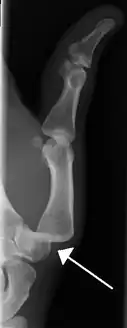

- Finger: Interphalangeal (IP) or metacarpophalangeal (MCP) joint dislocations[31]

Dislocation of the left index finger

Radiograph of left index finger dislocation